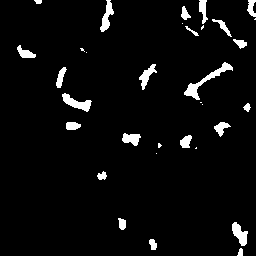

Semantic segmentation of blood vessels is an important task in medical image analysis, but its progress is often hindered by the scarcity of large annotated datasets and the poor generalization of models across different imaging modalities. A key aspect is the tendency of Convolutional Neural Networks (CNNs) to learn texture-based features, which limits their performance when applied to new domains with different visual characteristics. We hypothesize that leveraging geometric priors of vessel shapes, such as their tubular and branching nature, can lead to more robust and data-efficient models. To investigate this, we introduce VessShape, a methodology for generating large-scale 2D synthetic datasets designed to instill a shape bias in segmentation models. VessShape images contain procedurally generated tubular geometries combined with a wide variety of foreground and background textures, encouraging models to learn shape cues rather than textures. We demonstrate that a model pre-trained on VessShape images achieves strong few-shot segmentation performance on two real-world datasets from different domains, requiring only four to ten samples for fine-tuning. Furthermore, the model exhibits notable zero-shot capabilities, effectively segmenting vessels in unseen domains without any target-specific training. Our results indicate that pre-training with a strong shape bias can be an effective strategy to overcome data scarcity and improve model generalization in blood vessel segmentation.